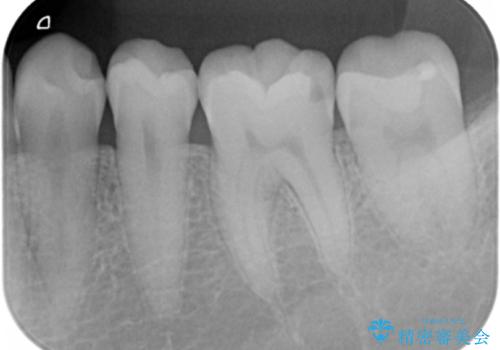

- 「他の医院で治療していたものの途中で放置していた奥歯が欠けたから治してほしい」とのことで来院。

食いしばりが強い自覚があり、「歯が欠けた理由も食いしばりです」とのことでした。

インレーが向かいの歯と強くかみ合ってしまったり、強い食いしばりがある場合はセラミックだと欠けてしまうリスクがあります。

今回の場合はセラミックインレーの部分に強くかみ合わないようかみ合わせの当たり具合を調整し、さらに夜間の食いしばりによってセラミックインレー・歯質が破折してしまわないようナイトガードの製作も行いました。